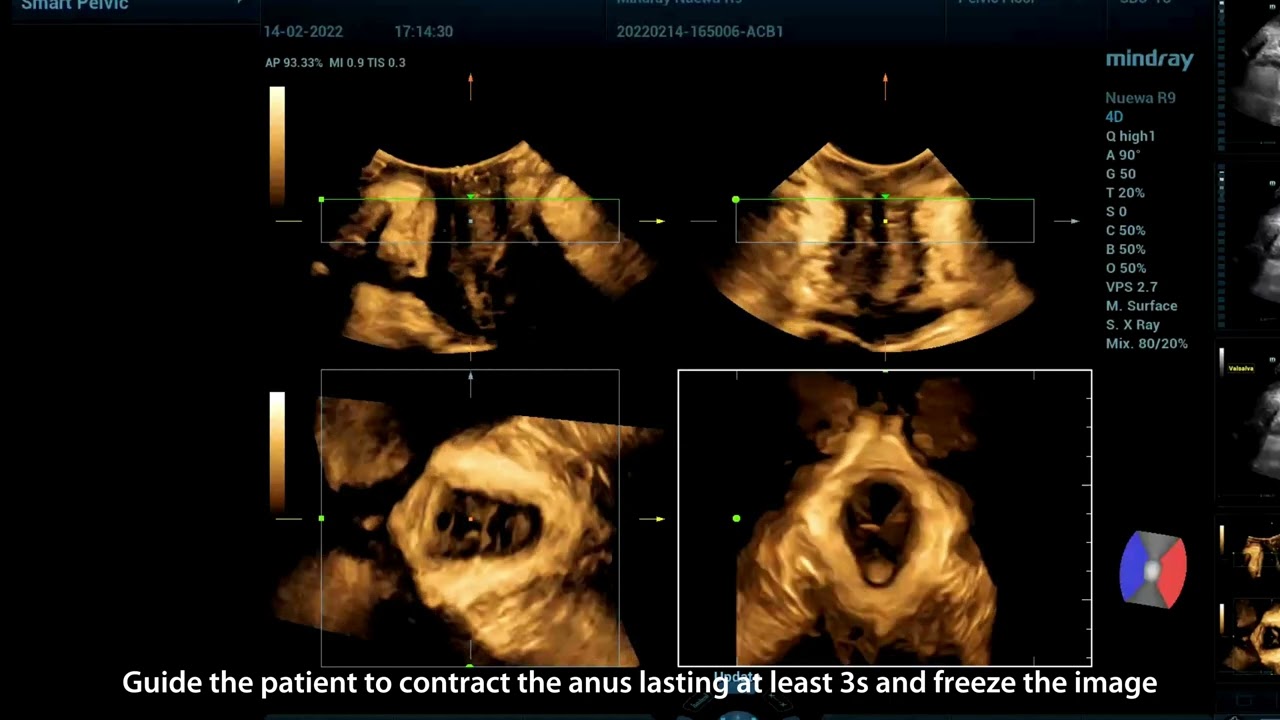

Bei der FPFD-Prognose mittels Ultraschall verfolgen ?rztinnen und ?rzte einen globalen Ansatz, der die umfassende, akkurate Diagnose der vorderen, mittleren und hinteren Teile des Beckens vorsieht, mit einer gro?en Zahl daf├╝r n?tiger 2D-Messungen, 3D-/4D-Bildgebung und Evaluationen usw. Die Untersuchung ist zeitaufwendig und unangenehm, was hohe Anforderungen an die Bildgebungsmodi und die Messgeschwindigkeiten stellt.

Nuewa bietet automatische 2D-Vermessungen der Beckenabschnitte sowie ein intelligentes Volumenberechnungssystem, einschlie?lich automatisierter Berechnung des Hiatus Levatorius und der Analyse mehrerer Abschnitte.